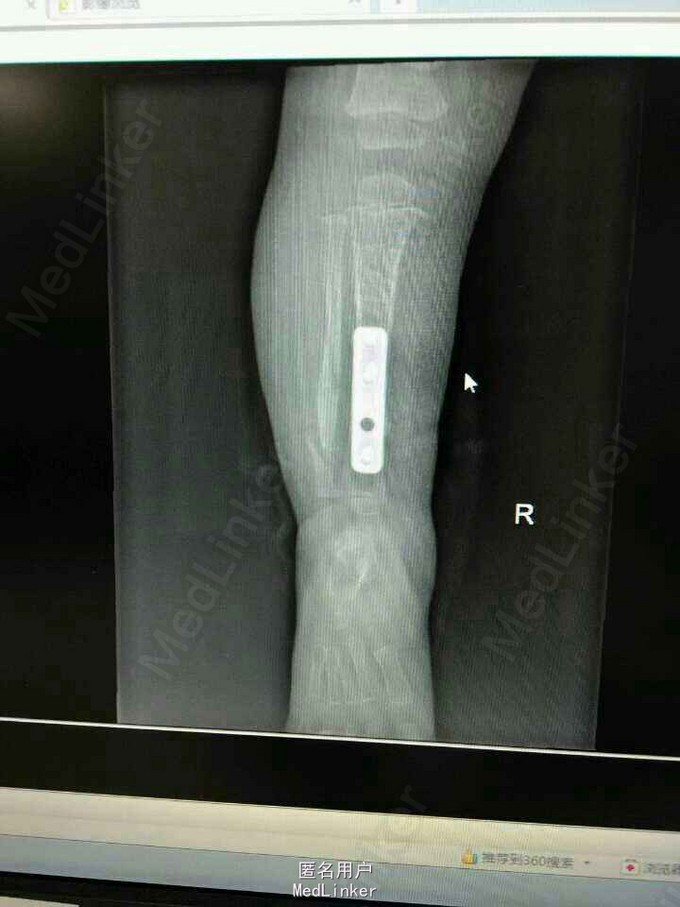

患女1岁8个月,患者母亲诉小孩出生时右小腿畸形,1岁时学走路跌倒后哭闹数天,小腿肿胀去医院检查示右胫腓骨折,稍做固定,1岁3个月时复查骨折未愈合,考虑先天性胫骨假关节,行手术治疗,现术后5个月复查未愈。目前小儿不能行走。

神经纤维瘤病,先天性胫骨假关节。该患者经过讨论及与家属多次沟通愈后情况,行病灶切除,取母体骨移植,AO锁定钢板内固定,暂时管型石膏外固定,并订制支具